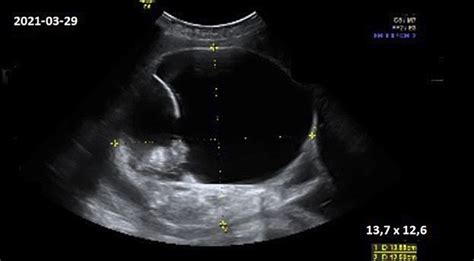

Tačiau, atsiradus naujiems neinvaziniams metodams, situacija keičiasi. Įvykus persileidimui, placentos audinys kurį laiką ir toliau išskiria laisvuosius (ne ląstelėse esančius) DNR fragmentus į motinos kraujotaką. Todėl, net ir ultragarsu nustačius persileidimo faktą, vis dar yra galimybė atlikti neinvazinę vaisiaus DNR analizę. Net jei vaisiaus DNR frakcija motinos kraujyje yra labai maža, specialus "Veritas" algoritmas leidžia ją aptikti ir išanalizuoti. Rekomendacija šiam tyrimui atlikti yra kuo greičiau po to, kai buvo pastebėta, kad nėštumas nutrūko, ir būtinai iki atliekant kiuretažo procedūrą, siekiant išsaugoti kuo daugiau vertingos informacijos.